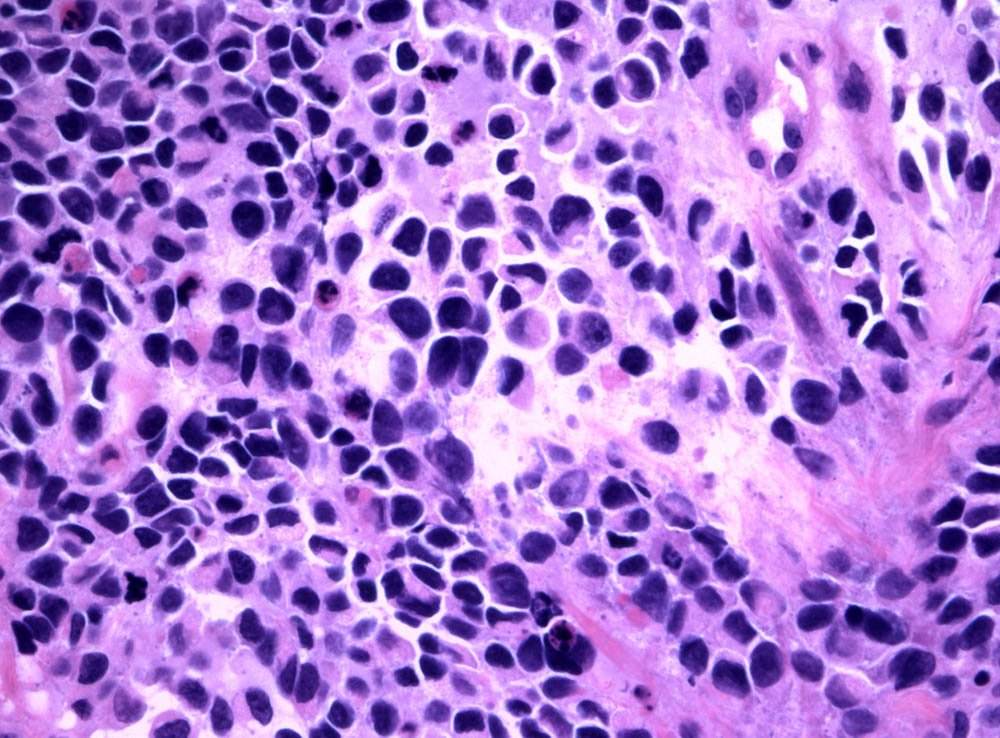

Case: ProstateMass

Specials to Order:

Final Diagnosis: